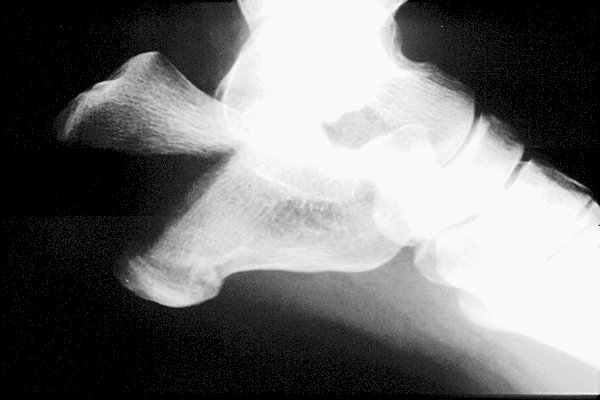

Return to Calcaneus Fracture